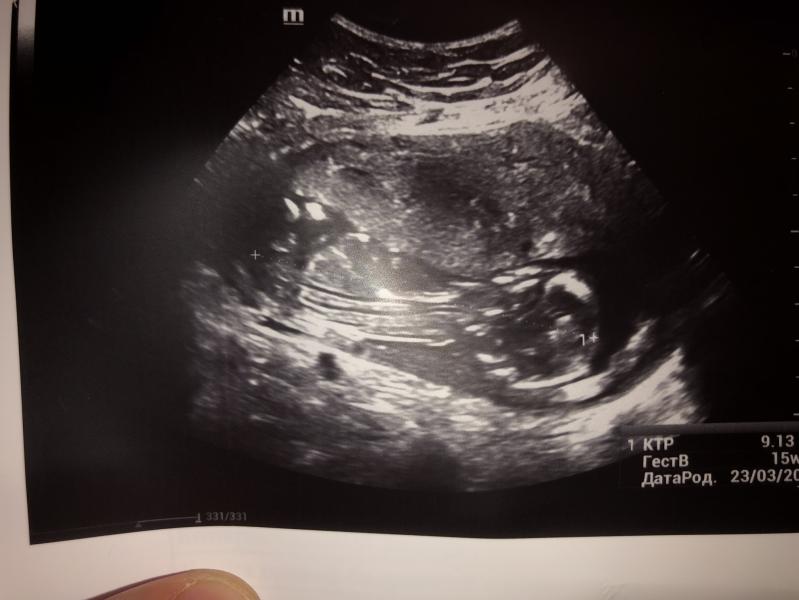

post image

На кого похожи?🙏

Аппарат просто ужасный и это в платной

Тут вообще ничего не понятно

Так и поняли, картинка не очень

Понятно, что хочет автор, но непонятно изображение от слова совсем 😂

Ну вроде пацан, плоховато видно

В принципе понятно где голова, где ножки, но на кого похож точно не скажем тут 🤗